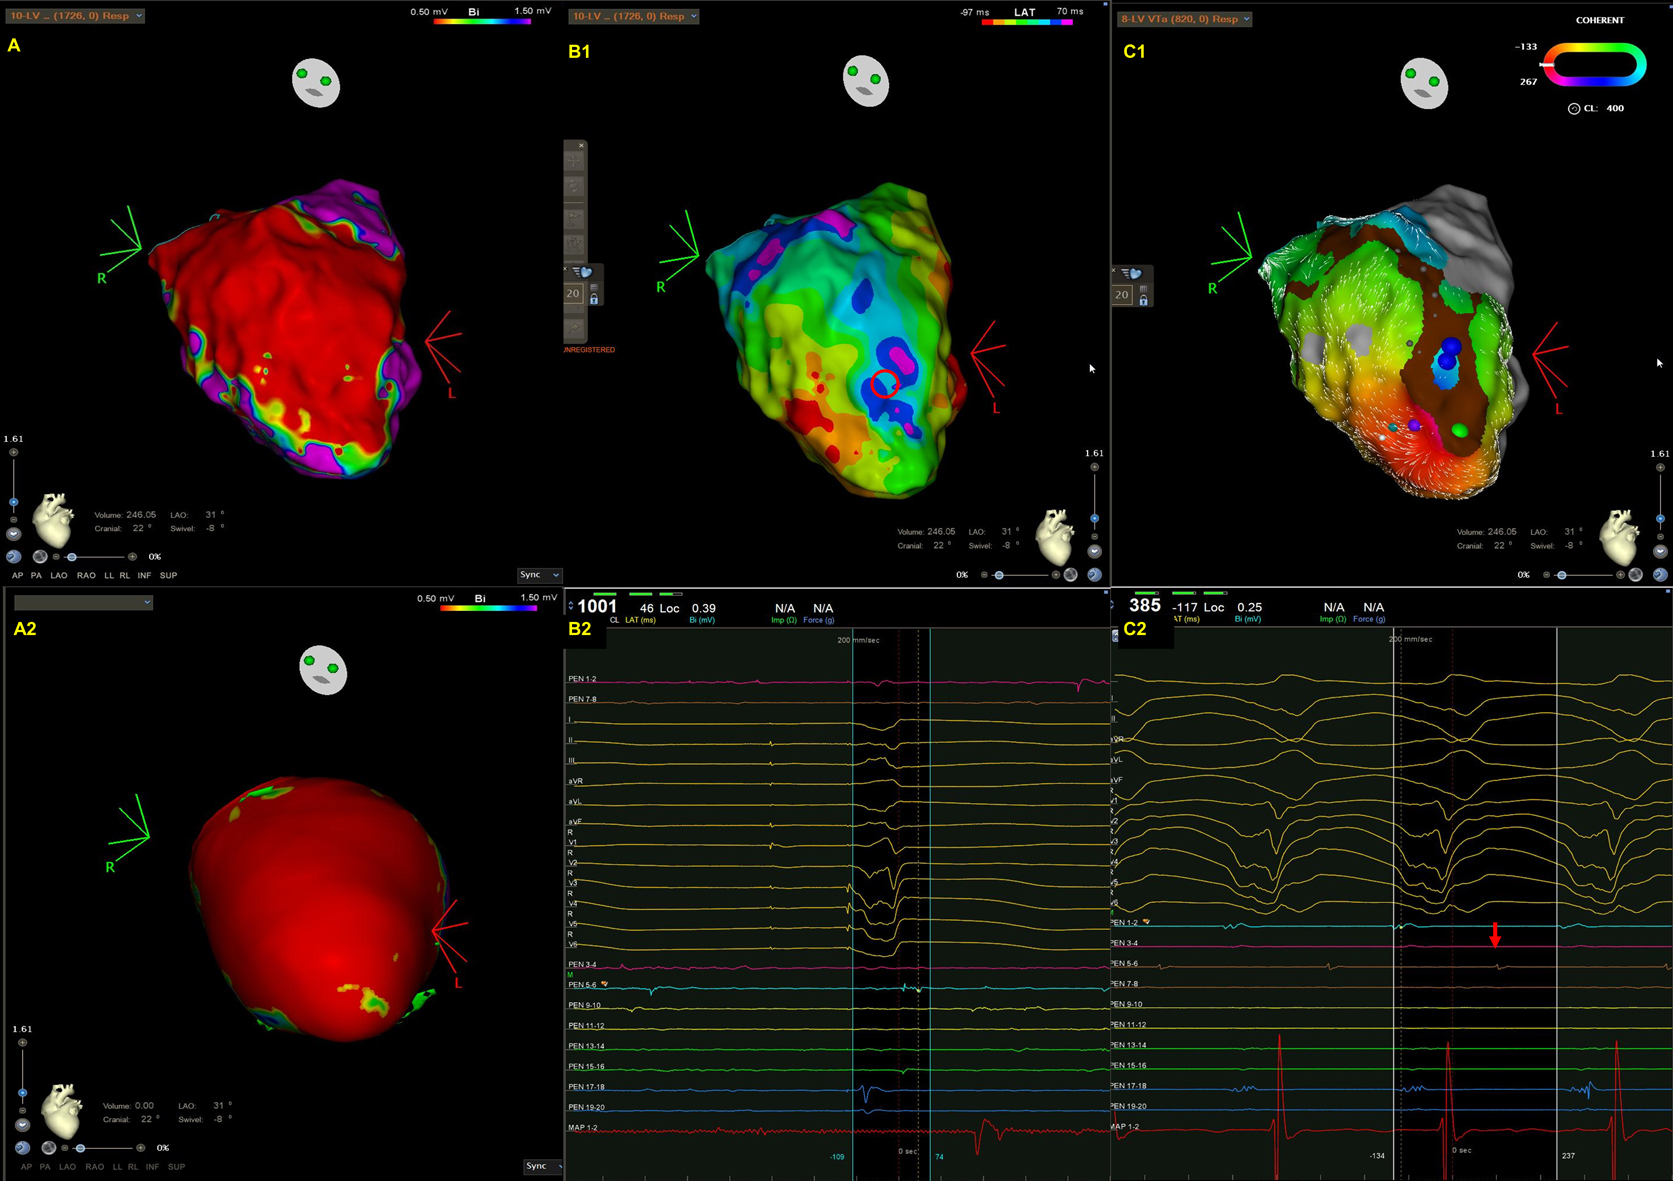

Cardiac sarcoidosis can affect RV, LV, or both [35, 36, 37, 38]. Patchy scarring is most often observed in the septum, followed by the anterior wall, the LV outflow tract, the inferior wall, the lateral wall, and the apex within the mid-myocardial and subepicardial layers of the LV, whereas scarring is generally seen in the RV [35, 36]. In addition, since the basal septum is frequently involved, right septal VTs, peritricuspid/perimitral VTs, or VTs originating from the Purkinje system are also common [37, 39]. A representative case was shown in Fig. 2.

Fig. 2.A representative case of focal VT in a patient with cardiac sarcoidosis. (A) An endocardial bipolar voltage map showed extensive scarring of the LV septum and inferior wall. (B) The spontaneous VT was characterized by a left bundle branch block pattern and superior axis. Wobbling of the VT cycle lengths was also noted. (C1–2) An isochronal late activation map (C1) was created by annotating the latest component of a bipolar electrogram. At the basal inferior portion of LV, there was an isochronal crowding region. (C2) The red asterisks indicate an isolated late potential (red arrow in C1) (D1–3). VT activation map (D1), the earliest electrogram during VT mapping (D2), and pacemapping at the earliest activation site (D3). The VT activation maps (D1, from red, orange, yellow, green, blue, indigo, to violet). Contrary to the majority of scar-related VTs, there was a centrifugal pattern of activation in this patient, indicating that the mechanism of VT in this case was focal rather than macroreentrant. There was a very early prepotential (D2, green arrow) preceding the onset of VT by 128 ms in the white asterisks area (D1) where was adjacent to the isochronal crowding region. During pacemapping, the QRS morphology at the earliest activation point was 96% similar to that of clinical VT. There was also a significant delay between the stimulus and QRS onset (121 ms) during pacemapping. The VT was terminated by ablation at this site.